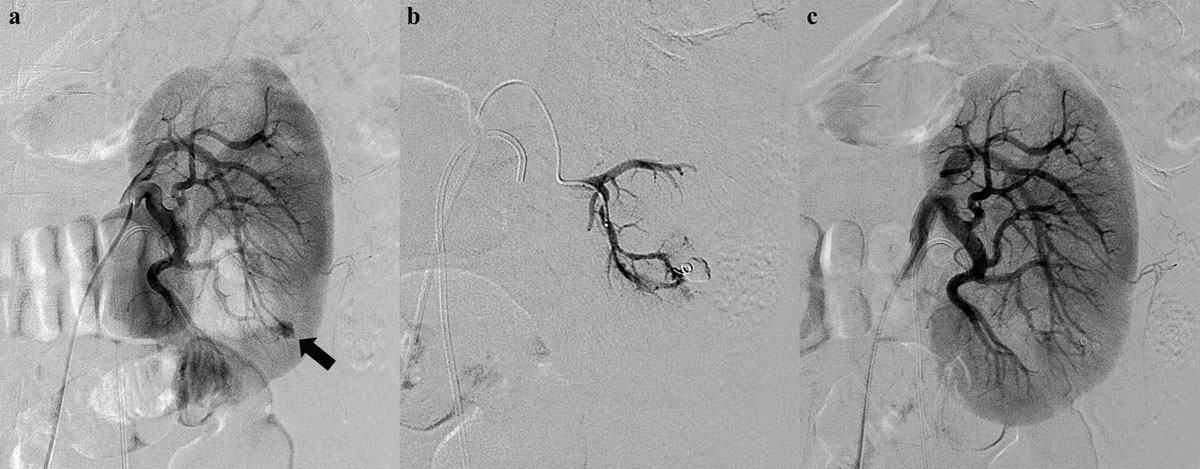

Figure 2

A 54-year-old man presenting with persistent hematuria after percutaneous nephrolithotomy. (a) An initial left renal angiogram shows a small pseudoaneurysm (black arrow) at arcuate branch of posterior segmental artery. (b) Superselective embolization of feeding artery using coaxial microcatheter system and a microcoil. (c) Postprocedural angiogram demonstrates complete devascularization of pseudoaneurysm.